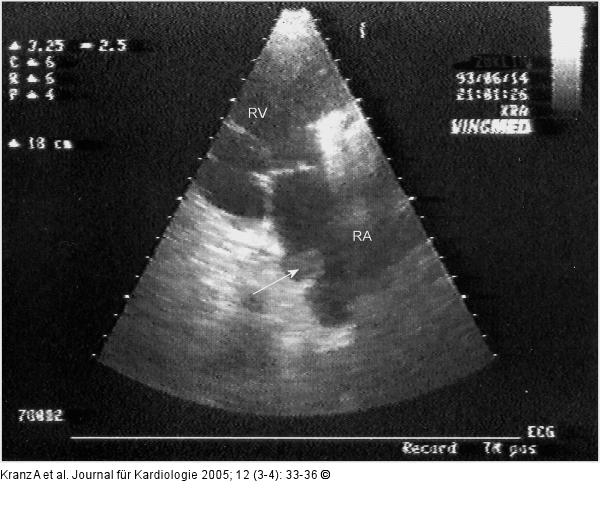

Abbildung 5: Kugelthrombus Kugelthrombus im Ostium des Sinus coronarius (Längsschnitt) |

Kugelthrombus im Ostium des Sinus coronarius (Längsschnitt) |